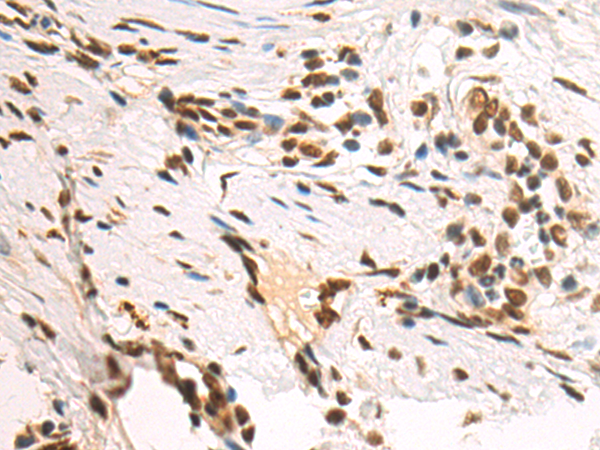

分类: 科研抗体货号: P09768别名: PTB; PTB2; PTB3; PTB4; pPTB; HNRPI; PTB-1; PTB-T; HNRNPI; HNRNP-I应用: WB,IHC反应种属: Human, Mouse, Rat